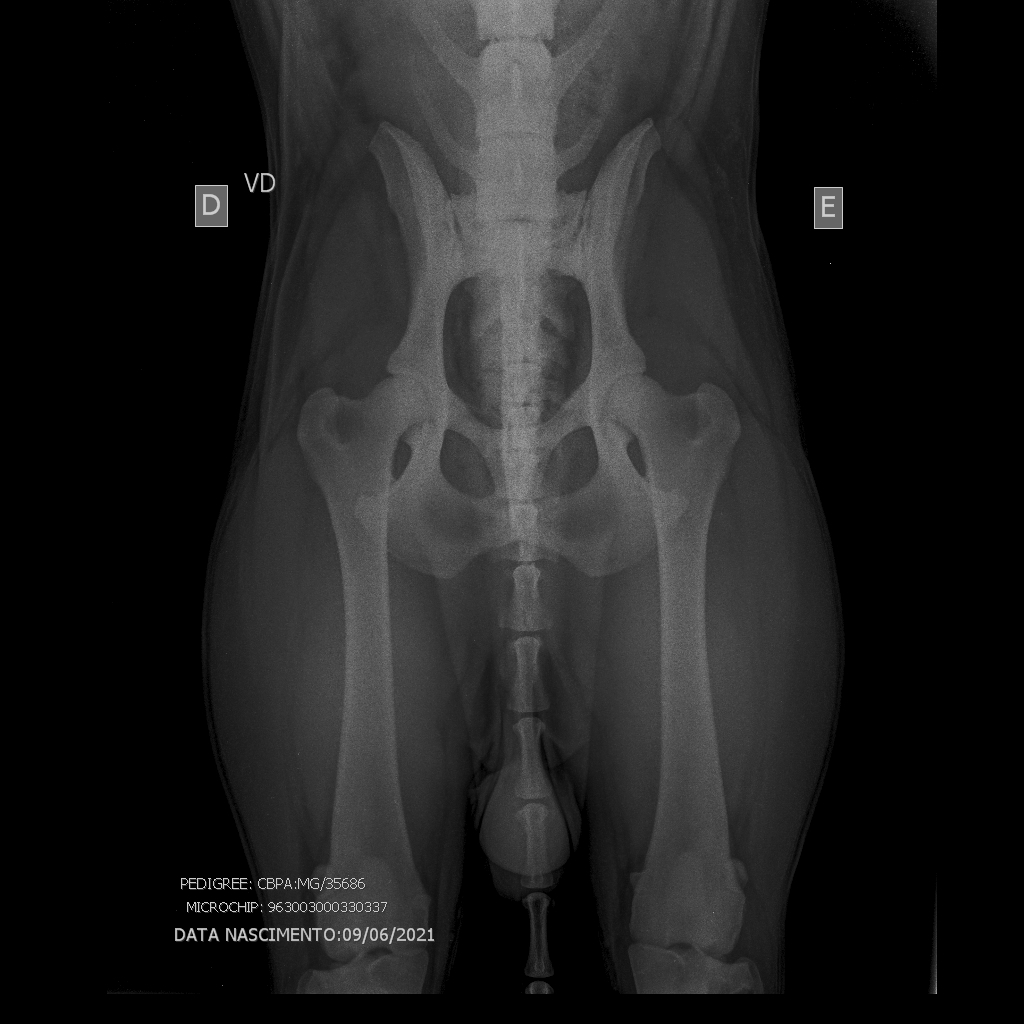

Raio X